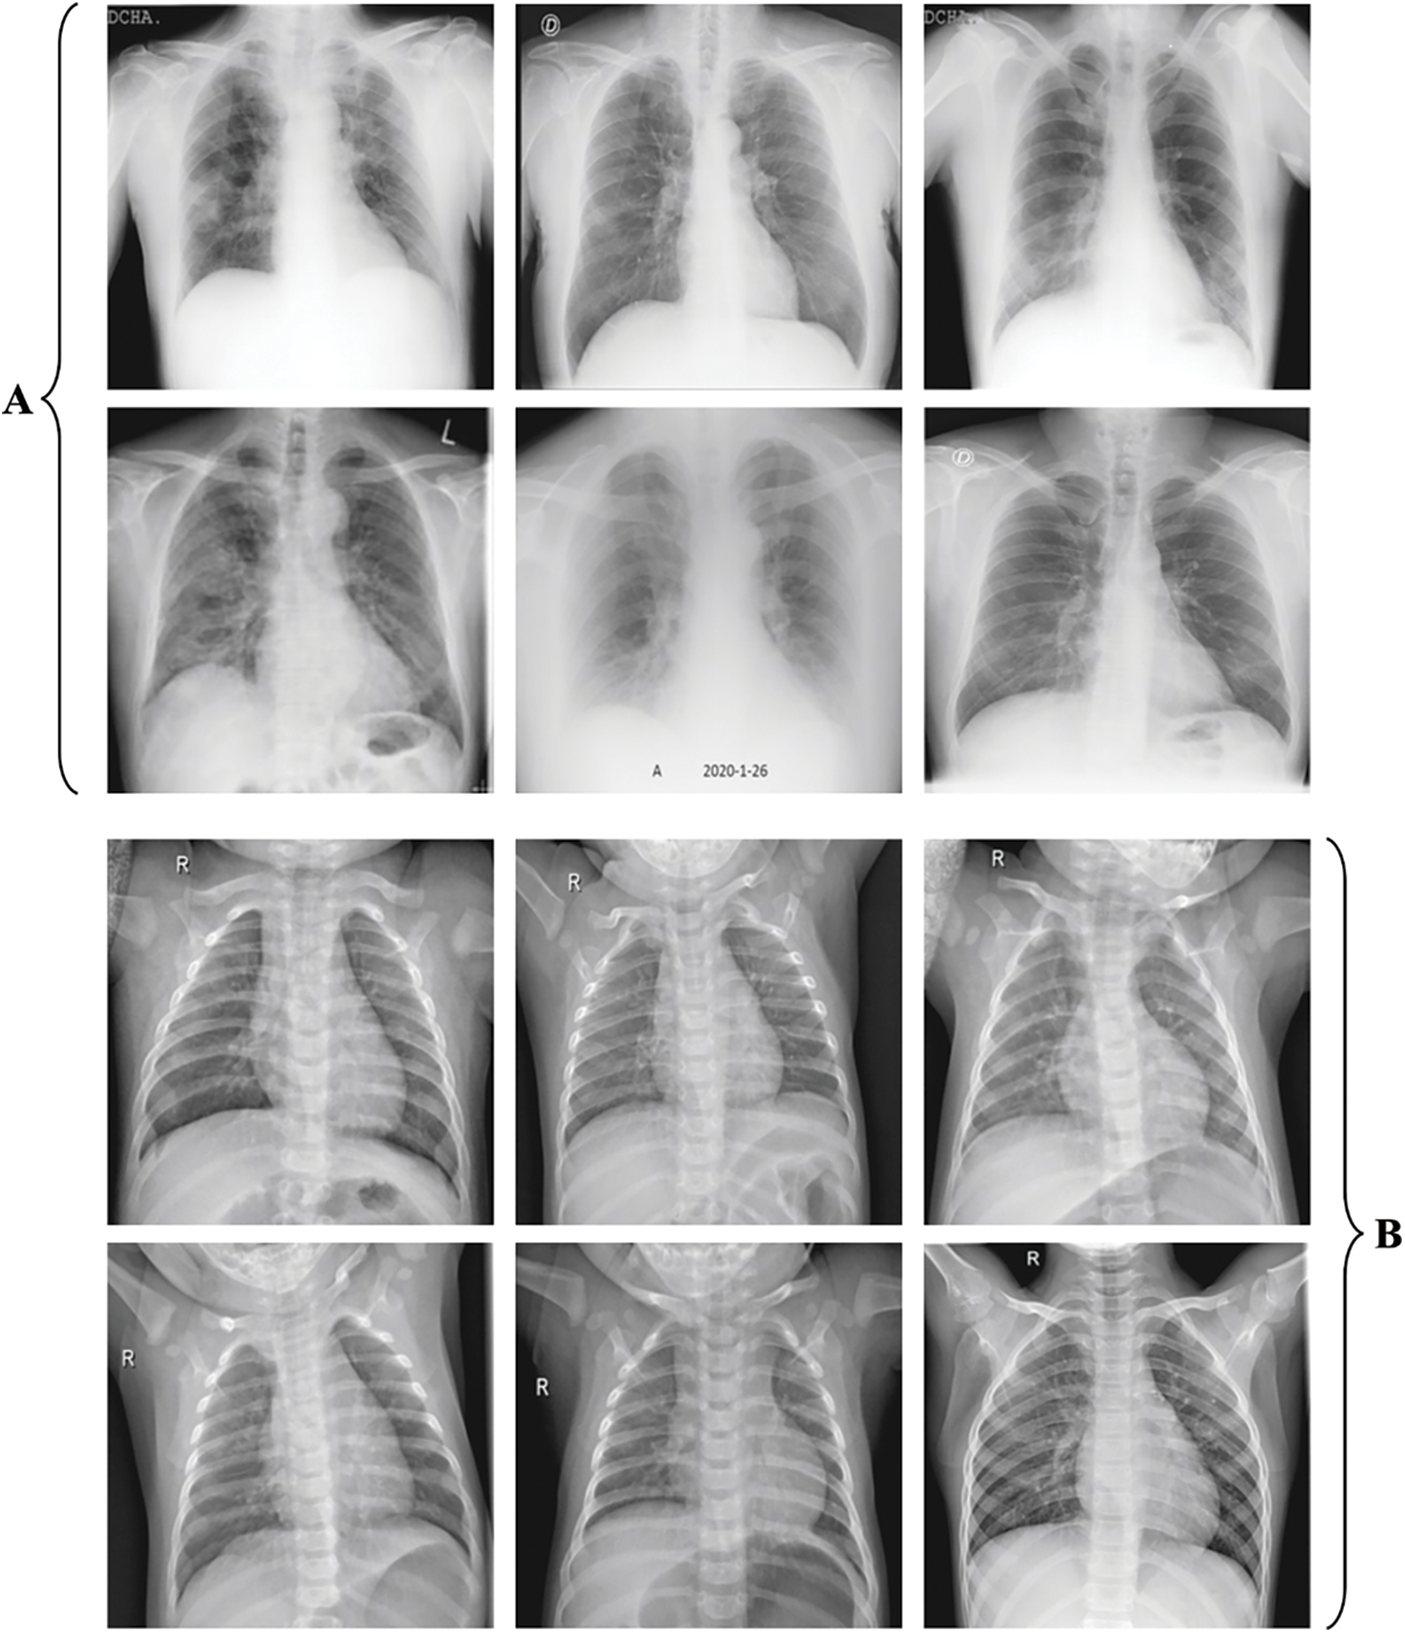

The experimental validation of the IFFA-DTLMS model is tested using the CXR image dataset [21], containing 32224 samples under COVID and 6448 samples under healthy class. A few image samples are illustrated in Fig. 3.

Figure 3: a) COVID b) Healthy